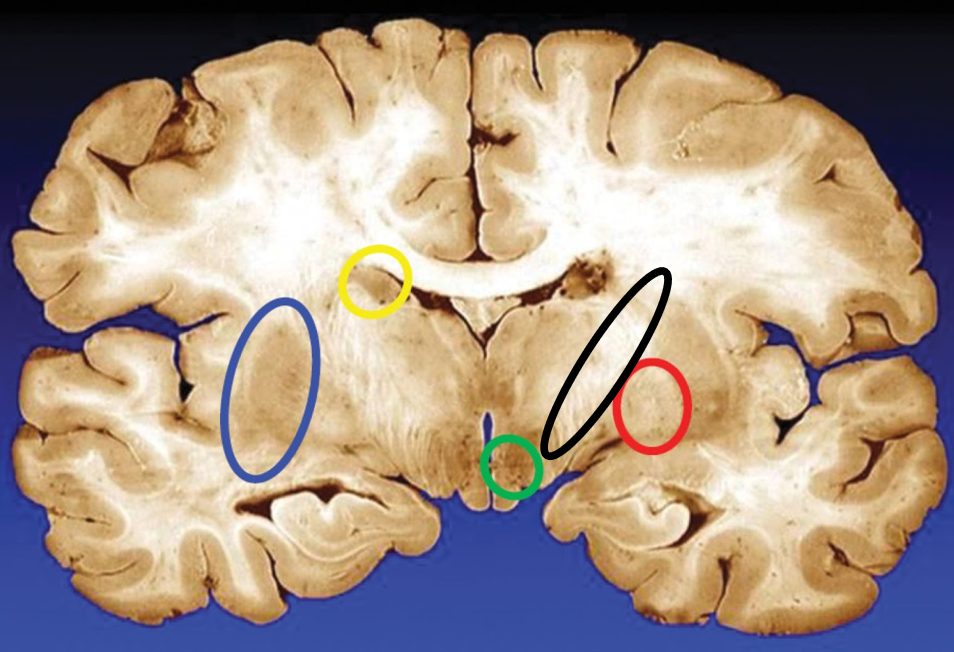

blue

putamen

yellow

caudate

green

subthalamic nuclei

black

internal capsule

red

globus pallidus

name the condition

Huntington’s (reduced caudate)